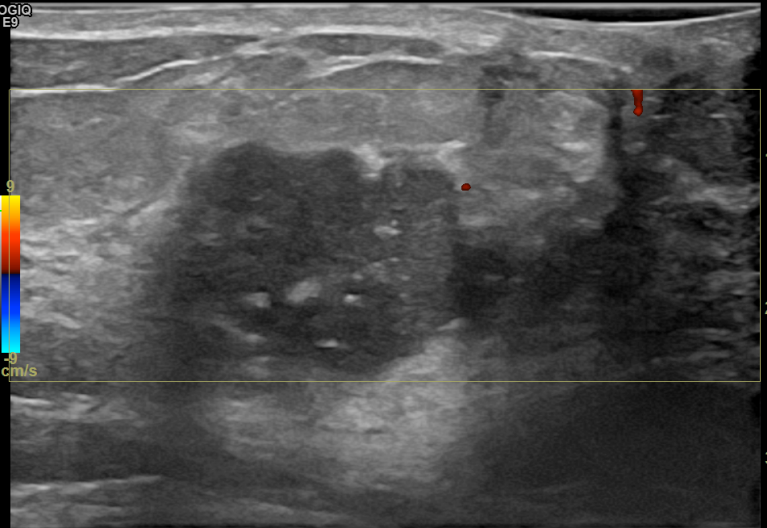

상기환자는 만져지는 멍울로 내원하신 40대후반

여성분으로 의심스러운 우측혹 조직검사 시행해 침윤성암으로 진단되었습니다